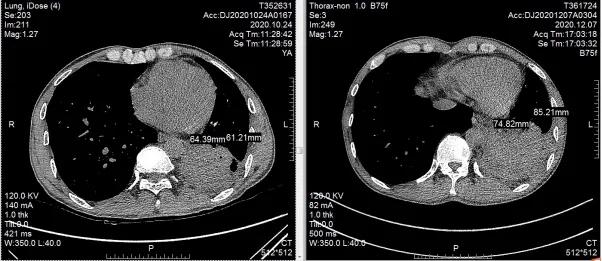

治疗12周复查胸部CT,双上肺部结核病灶较前较少,左下肺部肿瘤较前无大变化,肿瘤评估:稳定,但未再进展。抗痨治疗/抗肿瘤治疗期间,患者耐受性较好,无明显毒副反应,精神状态较前好转,咳嗽、咳痰症状明显减轻,痰涂转阴,极大增加了进一步治疗的信心。继续按原治疗方案行抗痨、抗肿瘤治疗,患者一般状况进一步好转,咳嗽/咳痰症状消失,24周复查胸部CT,双上肺结核病灶部分钙化,病情趋于稳定并向好的方向转归。左下肺肿瘤较前稍增大,肿瘤评估:稳定。

左下肺鳞癌,抗肿瘤治疗24周后病灶较前增大(纵膈窗)窗)